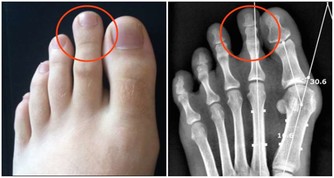

腫塊

癌細胞惡性增殖所形成的,有些可用手在體表或深部觸摸到。甲狀腺、腮腺或乳腺的癌可在皮下較淺部位觸摸到。